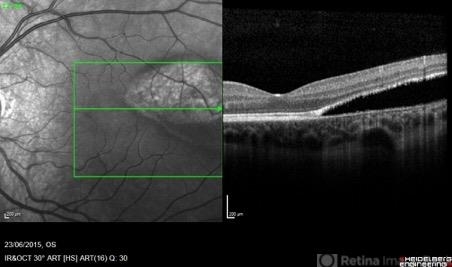

- torpedo maculopathy, optical coherence tomography (OCT)

- Pierre-Henry Gabrielle, Ophthalmology department, Dijon University Hospital, France

Optical coherence tomography system

Heidelberg Spectralis - Description

- Coupled OCT B-scan and IR imaging of an asymptomatic 12-year-old girl with torpedo maculopathy of the left eye. One can see that there is no involvement of the fovea which explain that the patient has no visual sign.